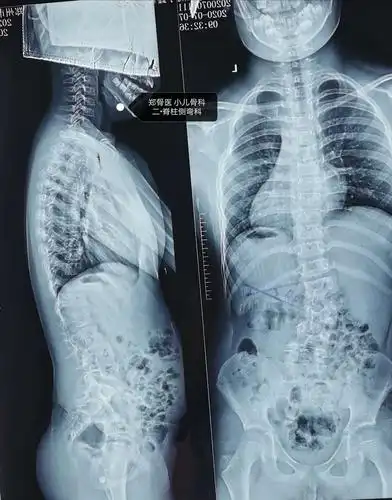

写作业老歪着身子14岁女生脊柱弯成s形

郑骨医,小儿骨科二脊柱侧弯科短阶段固定治疗脊柱侧弯一例